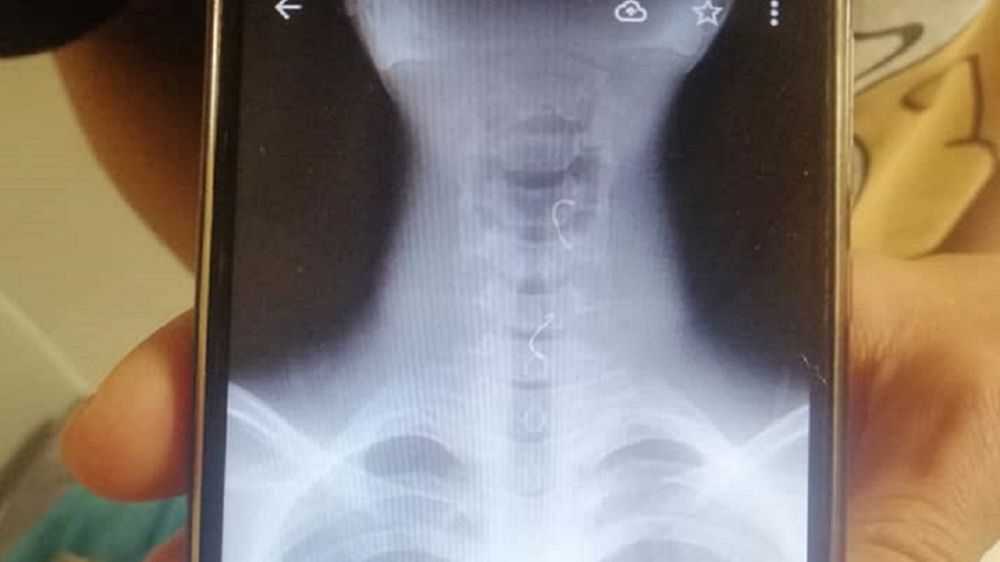

Do zdarzenia doszło w sobotę ok. godz. 17 przy ul. Nowopogońskiej w Czeladzi. 14-latek zadławił się przed sklepem elementami aparatu retencyjnego, które utknęły w jego przełyku.